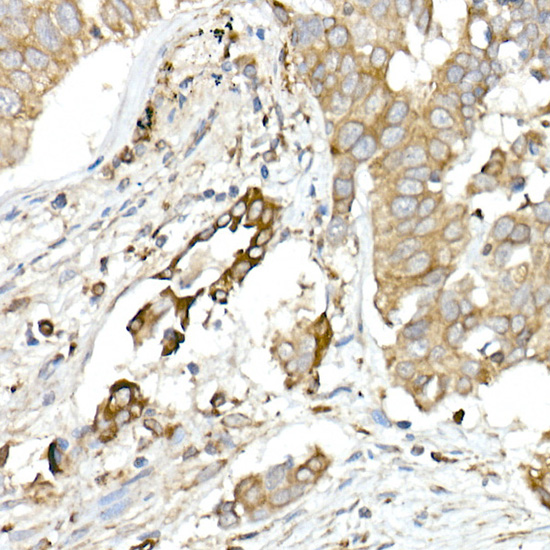

Immunohistochemistry of paraffin-embedded human colon carcinoma using MMP14/MT1-MMP Rabbit pAb.